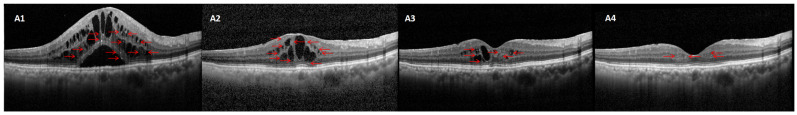

目的:探讨糖尿病性黄斑水肿(DME)患者玻璃体内注射雷尼单抗或地塞米松治疗后,光谱域光学相干断层扫描(SD-OCT)观察到的高反射点(HRDs)与预后的关系。方法:这项回顾性研究的重点是患有糖尿病黄斑水肿(DME)的个体,他们接受了连续三次玻璃体内注射雷尼单抗。根据治疗反应,将眼睛分为两组:反应者和无反应者。无反应组随后接受玻璃体内地塞米松(IVO)植入。通过BCVA、HRD数和中央黄斑厚度(CMT)的变化来评估治疗结果。结果:这项研究涉及78名被诊断患有二甲醚的参与者的112只眼睛。73只眼睛(65%)被确定为雷尼单抗应答,39只眼睛(35%)被确定为雷尼单抗无应答。在对雷尼单抗反应不佳并随后接受玻璃体内地塞米松植入治疗的39例患者中,26只眼(66.67%)表现出良好反应,而13只眼(33.33%)表现出反应不足。IVR应答者在BCVA(0.54±0.73 ~ 0.35±0.40 logMAR vs. 0.52±0.61 ~ 0.47±0.38 logMAR)和CMT(456.53±109.73 μm ~ 235.47±49.13 μm vs. 468.99±127.10 μm ~ 427.45±52.91 μm)降低方面表现出更大的改善。基线分析显示,与应答者相比,IVR无应答者的视网膜内外部hrd计数更高(分别为9.09±3.38 vs. 7.07±2.32和5.46±2.03 vs. 4.27±1.87,p < 0.05)。初始视网膜内、外、下HRDs数量较高的眼睛对地塞米松治疗的反应显著增强(分别为9.03±3.18 vs. 7.55±2.72,6.55±2.46 vs. 4.79±1.88,0.27±0.54 vs. 0.21±0.47,p < 0.05)。结论:HRDs可能作为一种预测性生物标志物,用于评估抗vegf治疗DME的有效性。表现出更多视网膜hrd的患者往往对抗vegf治疗反应较差,但地塞米松治疗效果较好。

Objectives: To evaluate the relationship between hyperreflective dots (HRDs) observed on spectral-domain optical coherence tomography (SD-OCT) and the outcomes following treatment with intravitreal ranibizumab or dexamethasone injections in patients with diabetic macular edema (DME). Methods: This retrospective study focused on individuals suffering from diabetic macular edema (DME) who underwent a sequence of three intravitreal ranibizumab injections. Based on treatment response, the eyes were categorized into two groups: responders and non-responders. The non-responder group subsequently received intravitreal dexamethasone (IVO) implants. Treatment results were evaluated by changes in BCVA, HRD number, and central macular thickness (CMT). Results: This research involved 112 eyes from 78 participants who had been diagnosed with DME. Seventy-three eyes (65%) were identified as ranibizumab responders and 39 eyes (35%) as ranibizumab non-responders. Of the 39 individuals who had suboptimal response to ranibizumab and subsequently received treatment with an intravitreal dexamethasone implant, 26 eyes (66.67%) exhibited a favorable response, while 13 eyes (33.33%) showed an insufficient response. IVR responders demonstrated significantly greater improvements in BCVA (0.54 ± 0.73 to 0.35 ± 0.40 logMAR vs. 0.52 ± 0.61 to 0.47 ± 0.38 logMAR) and CMT (456.53 ± 109.73 μm to 235.47 ± 49.13 μm vs. 468.99 ± 127.10 μm to 427.45 ± 52.91 μm) reduction. Baseline analysis revealed IVR non-responders had higher counts of both inner and outer retinal HRDs compared to responders (9.09 ± 3.38 vs. 7.07 ± 2.32 and 5.46 ± 2.03 vs. 4.27 ± 1.87, p < 0.05, respectively). Eyes with initially higher numbers of inner retinal HRDs, outer retinal HRDs, and subretinal HRDs demonstrated a significantly enhanced response to dexamethasone therapy (9.03 ± 3.18 vs. 7.55 ± 2.72, 6.55 ± 2.46 vs. 4.79 ± 1.88 and 0.27 ± 0.54 vs. 0.21 ± 0.47, p < 0.05, respectively). Conclusions: HRDs could potentially be used as a predictive biomarker to assess the effectiveness of anti-VEGF therapy in treating DME. Patients exhibiting a greater number of retinal HRDs tend to have less favorable reactions to anti-VEGF treatments but experience improved results with dexamethasone.